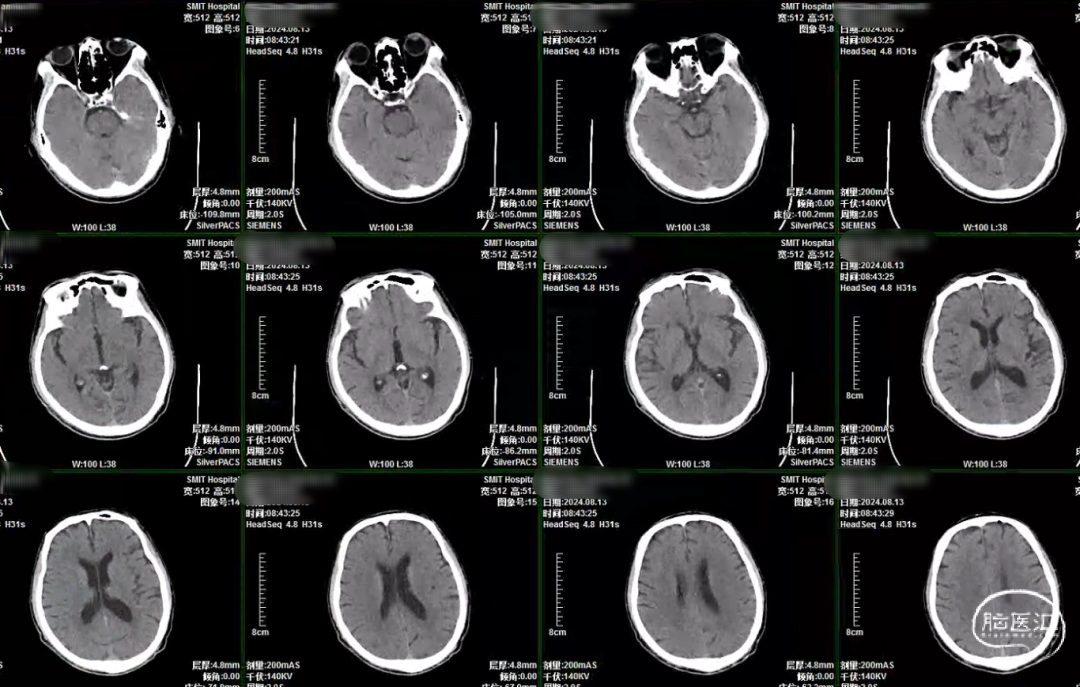

CT:

CTA提示:右侧颈内动脉起始部重度狭窄。